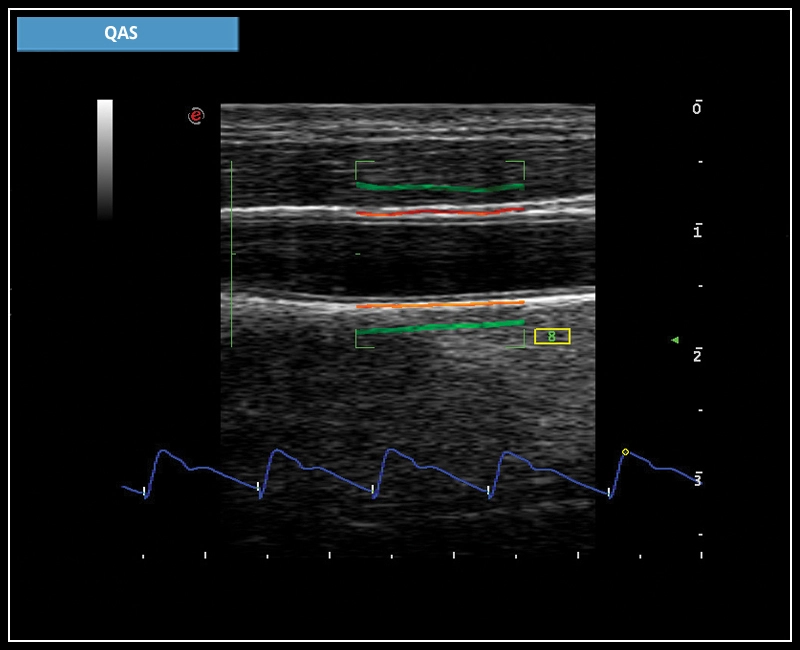

MyLab™X7 - QAS

MyLab™X7 - QAS